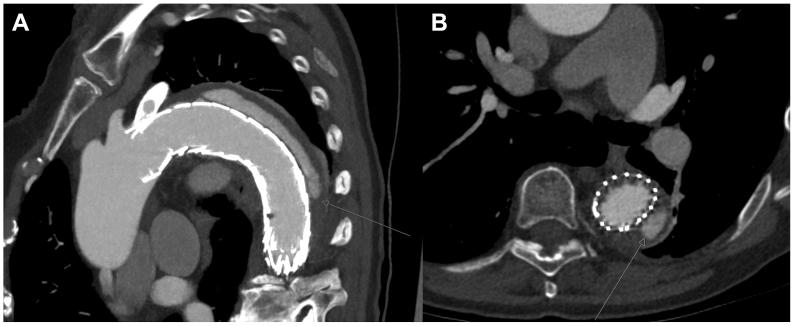

This report describes the treatment of a gutter-related type Ia endoleak after chimney thoracic endovascular aortic repair to the left subclavian artery. The aneurysm sac was accessed via direct percutaneous transthoracic puncture, followed by selective catheterization of the gutter. Angiography confirmed the endoleak, which was treated with coil embolization. Track embolization was performed using Histoacryl glue. Follow-up computed tomography angiography demonstrated complete resolution of the endoleak. Percutaneous transthoracic coil embolization seems to be a feasible and effective treatment for gutter-related type Ia endoleak after chimney thoracic endovascular aortic repair. Given the anatomical complexity and variation in access options, treatment strategies should be individualized.

本报告描述了在经烟囱技术行胸段主动脉腔内修复术至左锁骨下动脉后,对与肋间沟相关的Ia型内漏的治疗。通过直接经皮经胸穿刺进入瘤腔,随后对肋间沟进行选择性插管。血管造影证实了内漏,采用弹簧圈栓塞进行治疗。使用组织黏合剂进行追踪栓塞。随访计算机断层扫描血管造影显示内漏完全消失。经皮经胸弹簧圈栓塞似乎是经烟囱技术行胸段主动脉腔内修复术后与肋间沟相关的Ia型内漏的一种可行且有效的治疗方法。鉴于解剖结构的复杂性和入路选择的差异,治疗策略应个体化。